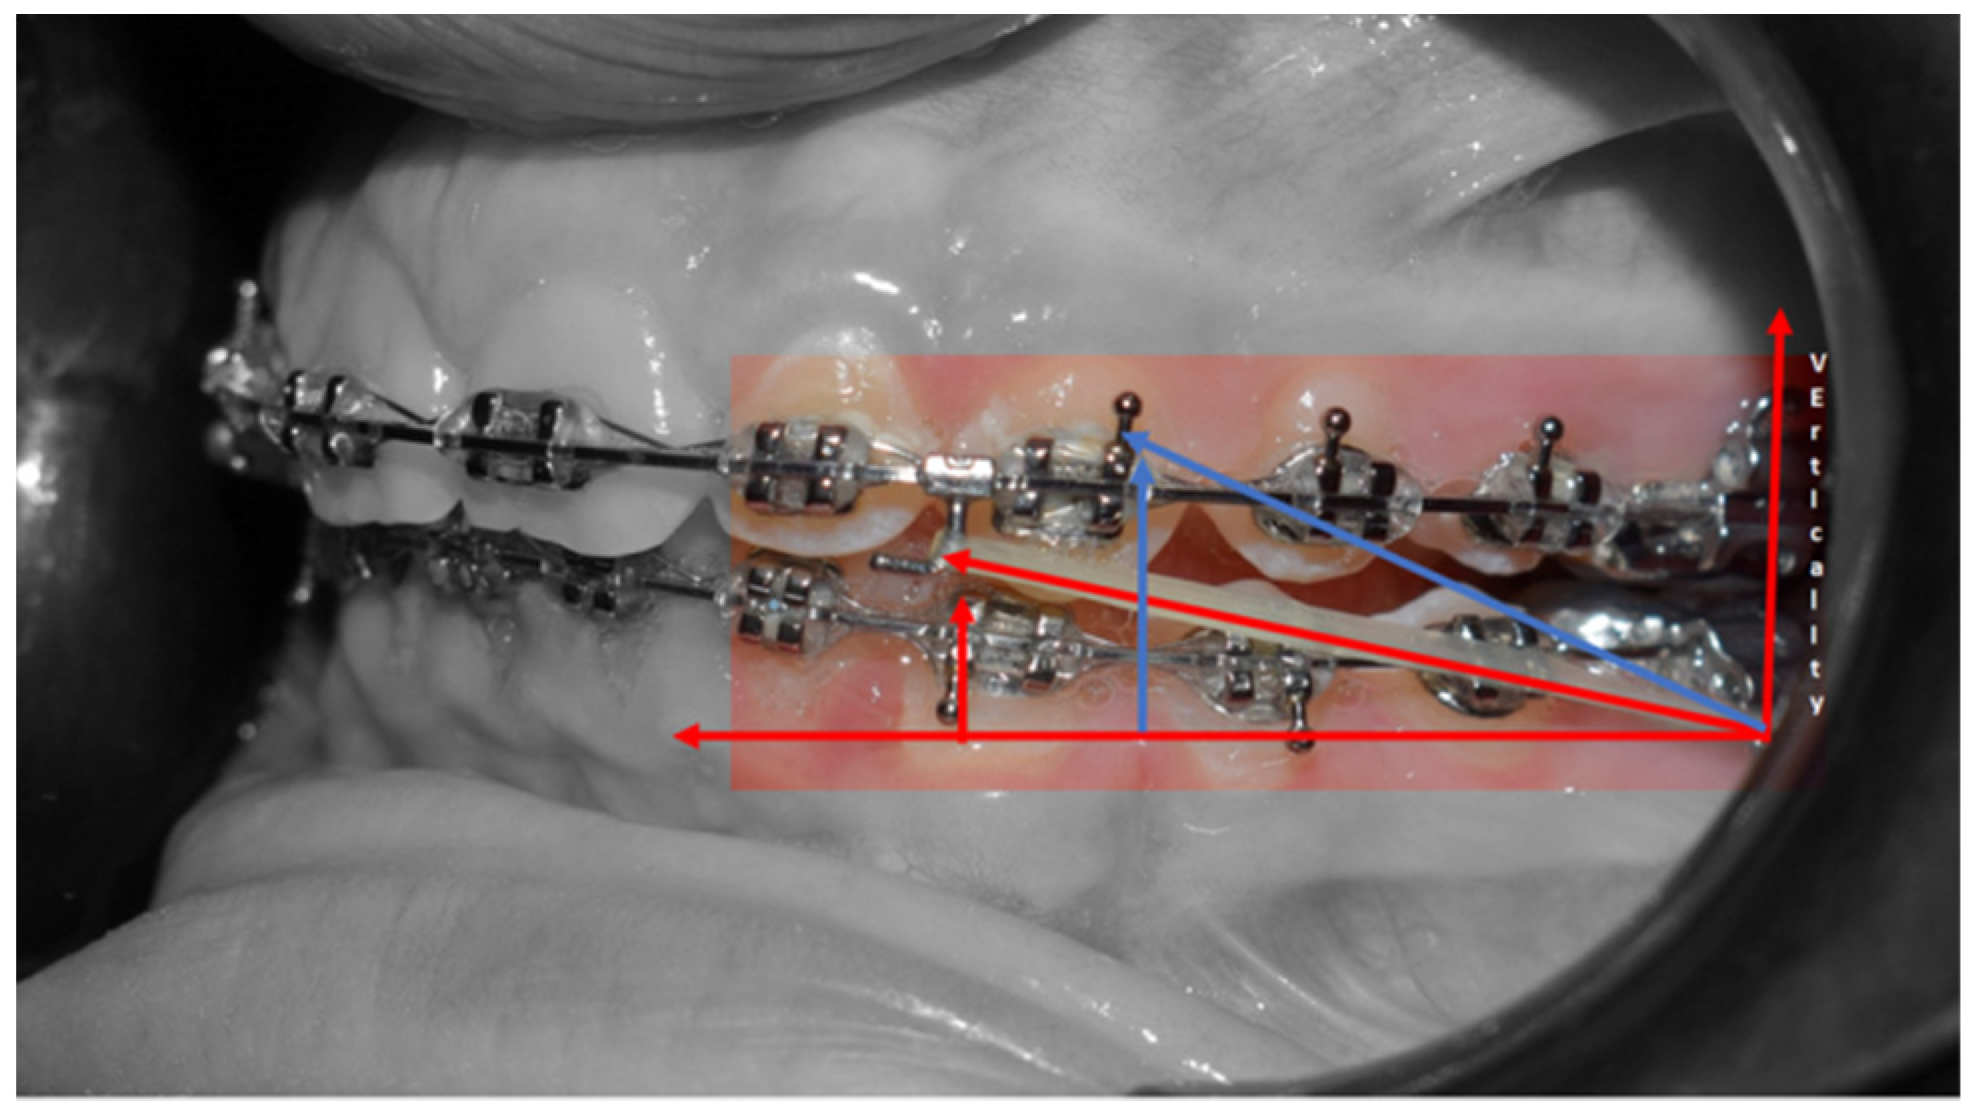

- Reverse Pin System” was placed on 13 and 23 to initiate class II biomechanics. Class II elastics (upper canines and first inferior molars) 3/8 4.5 ounces were used (Figure 3c). Class II elastics were used for 18 h every day;